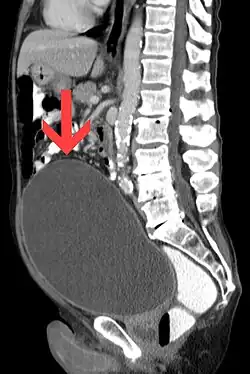

Urinary retention with greatly enlarged bladder as seen by CT scan.